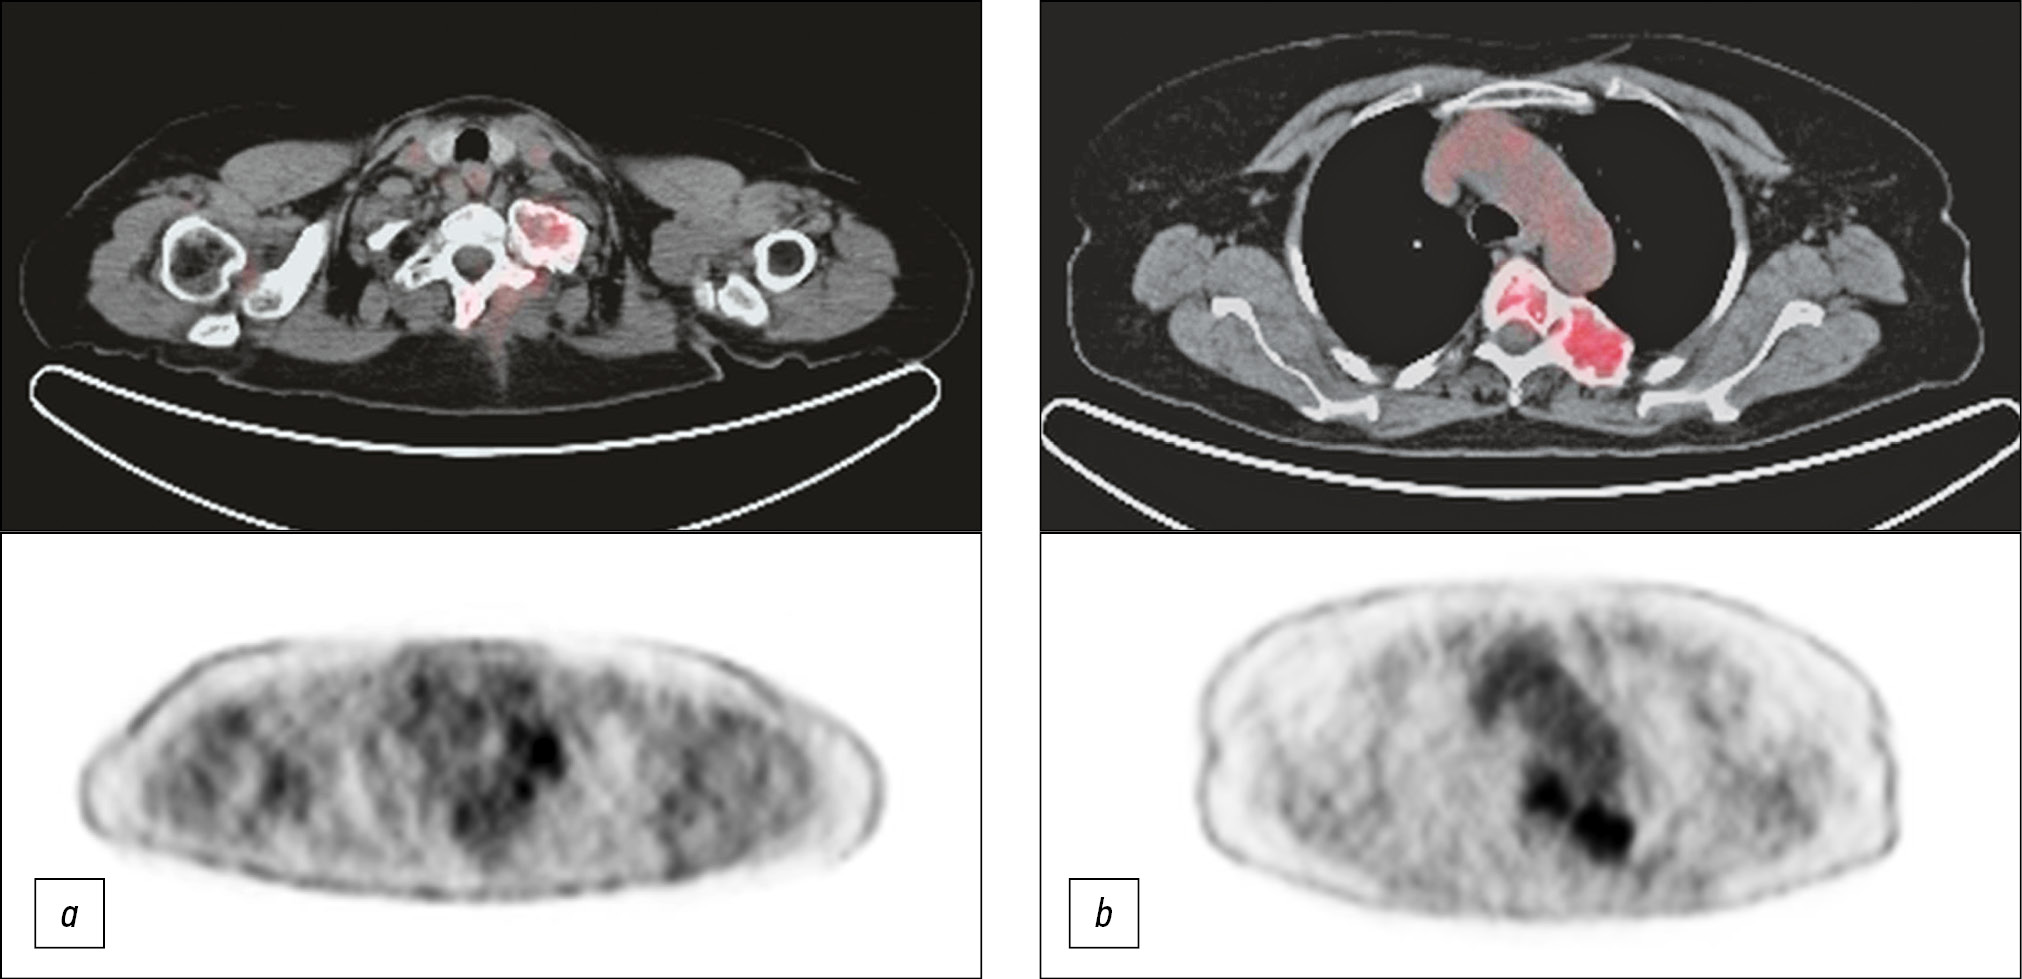

本文描述了一名65岁的患者,她因主诉颈部和背部疼痛而入住我们的放射科。此前,该患者被诊断为颈部和胸部骨骼病变,疑似转移。在我科,该患者先前被诊断为纤维异样增殖症,随后通过X射线、计算机断层扫描和磁共振成像确认。最终诊断是基于骨活检的结果。